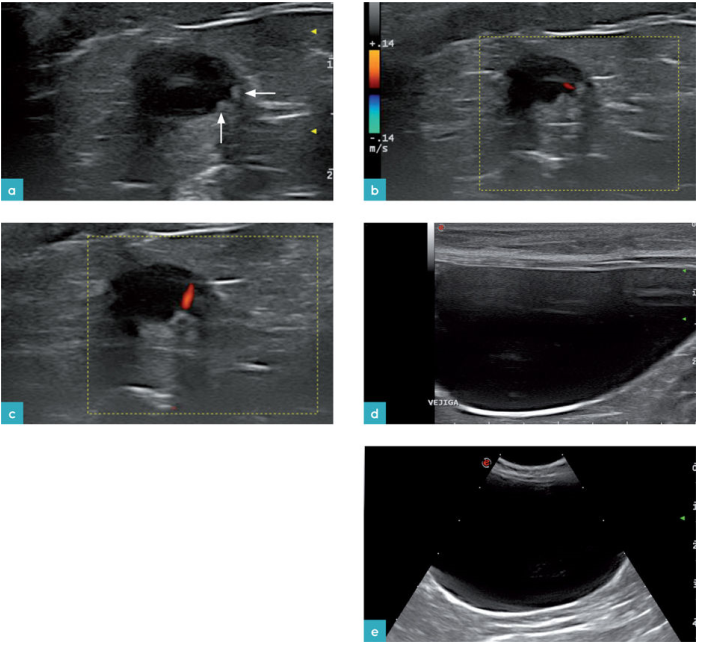

膀胱三角区或者称为膀胱颈与膀胱的其他区域是没有明显的界限划分,就是一个位于膀胱的后方进入尿道前的圆锥形区域。输尿管乳头开口在膀胱三角区内,呈现小的突起,不要认为是异常。尿液从输尿管乳头进入膀胱,二维上可见到到高回声的尿液射流,使用彩色多普勒可以看到彩色的位移信号(图1)。